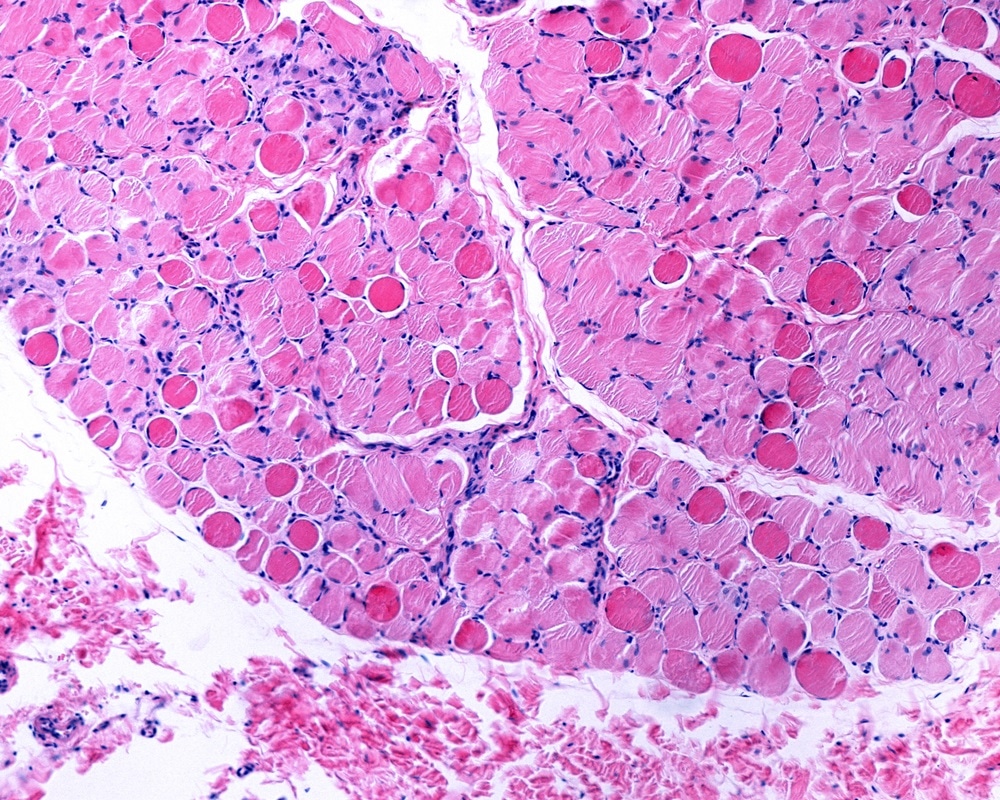

Duchenne muscular dystrophyImage Credits: Jose Luis Calvo / Shutterstock.com